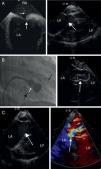

Elective PMBV was scheduled. Standard right heart catheterization was initially performed to invasively assess right heart pressures. Through a second right transfemoral venous access, the ICE catheter probe was advanced to the mid segment of the right atrium in order to visualize the atrial septum and guide the transeptal puncture. All septal borders were assessed before and during the tenting of the septum with the Mullin catheter (Figure 1A). After identification of the optimal interatrial septal position for puncture, the Brockenbrough needle and the sheath were advanced to the left atrium. With angiographic and ICE guidance the mitral valve balloon was advanced and inflated (Figure 1B). Immediate assessment of the post-procedural mitral valve morphology, transmitral valve gradient and mitral regurgitation were performed by fluoroscopy and ICE (Figure 1C).

(A) Left: ICE image showing tenting of the interatrial septum (large white arrow) with the Mullins catheter and Brockenbrough needle (small white arrow). LA: left atrium; RA: right atrium. Right: ICE 2-chamber view after insertion of the ICE probe into the right ventricle (RV). Visualization of the mitral valve (white arrow) prior to percutaneous mitral balloon valvuloplasty. Left atrial enlargement and left ventricular function and dimensions can be assessed. (B) Percutaneous mitral balloon valvuloplasty. Angiographic and ICE visualization of the inflated Inoue balloon (white arrow). ICE catheter probe (large black arrow) is located in the RV and the pig-tail catheter (small black arrow) in the left ventricle. (C) Post-PMBV ICE assessment. Left: two-dimension assessment. Right: Doppler evaluation of the mitral valve showing 1+ mitral regurgitation.